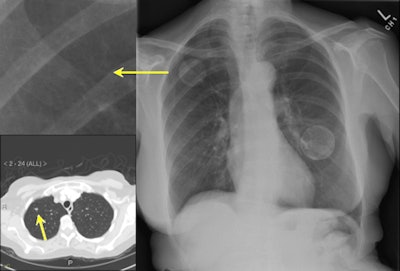

| IQQA-Chest software (right) identified two areas of potential interest. A magnified view (upper left) reveals a subtle mass; suspicious lung nodule later confirmed by CT (lower left) in renal cell cancer patient. The region of interest in the left lobe is a false positive. Image provided by EDDA Technology. |